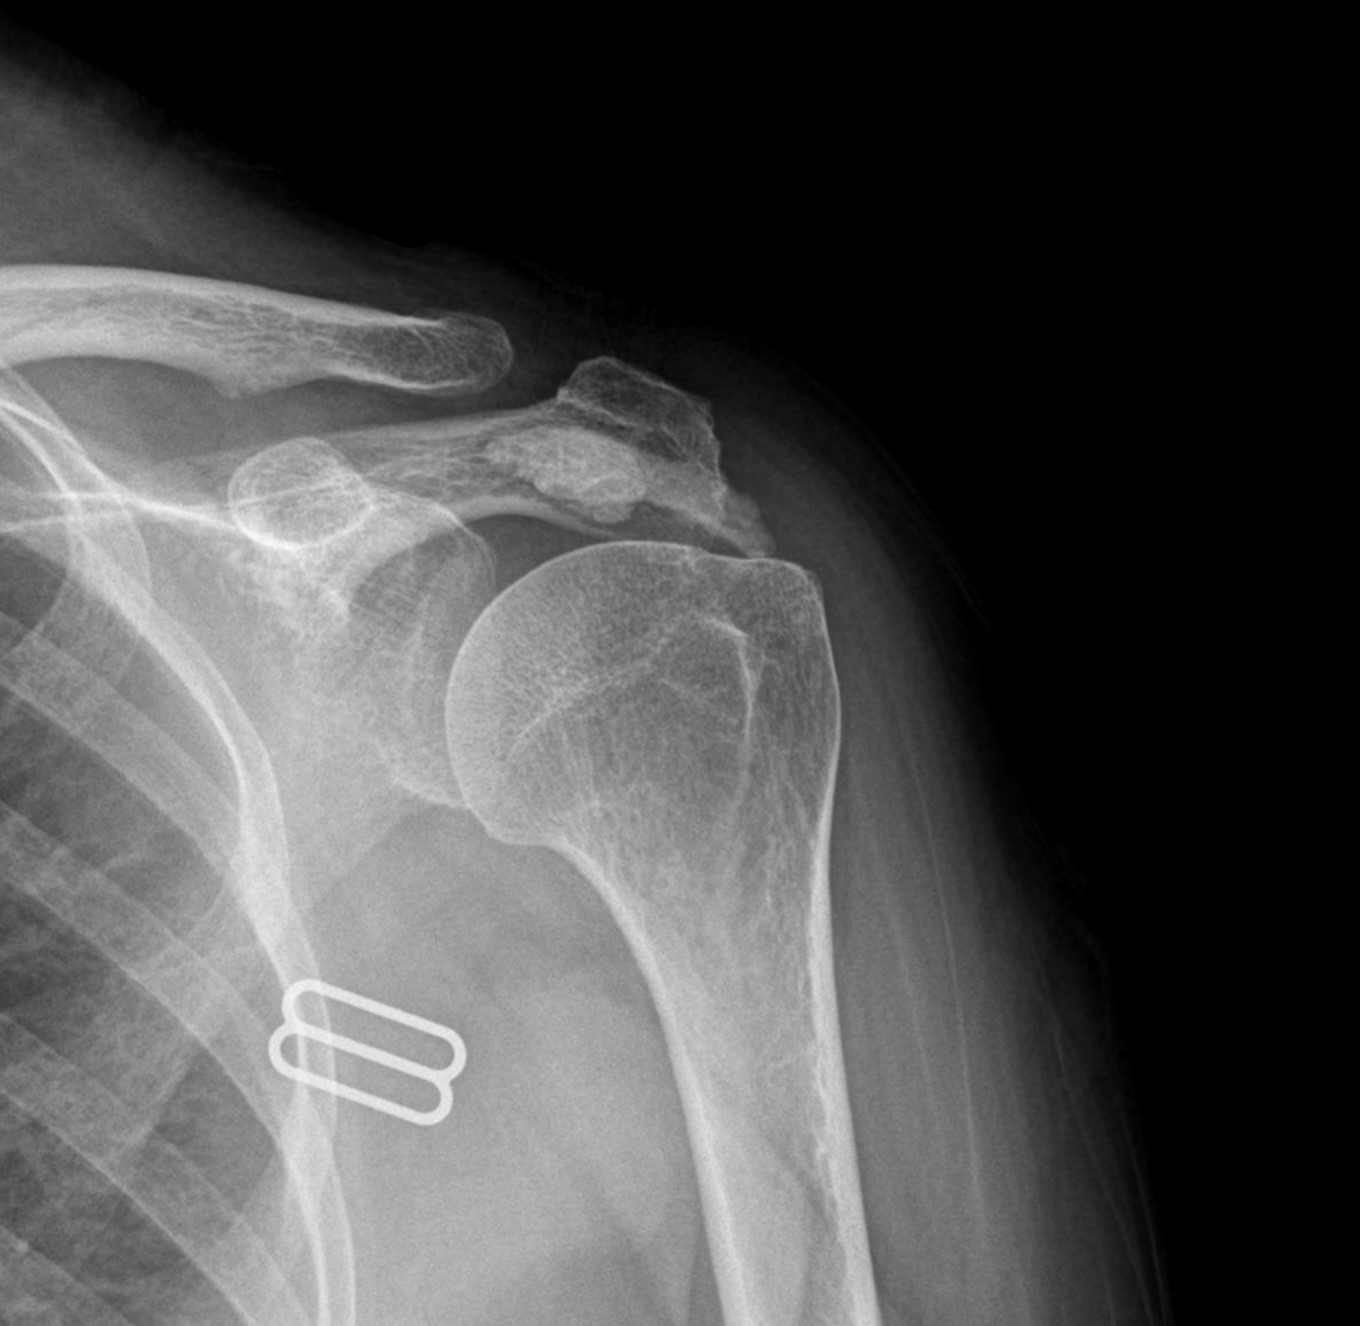

케이스 3: 흡수기 대형 석회 (1회 제거)

환자: 30대 여성, 임신 5개월, 양측 어깨 통증

특이사항:

임신 중이라 X-ray, 전신마취 불가

참을 수 없는 통증으로 시술 결정

시술:

국소마취 하 분쇄흡입술

1.6cm 흡수기 석회 1회 제거

타 병원 실패 후 내원 케이스